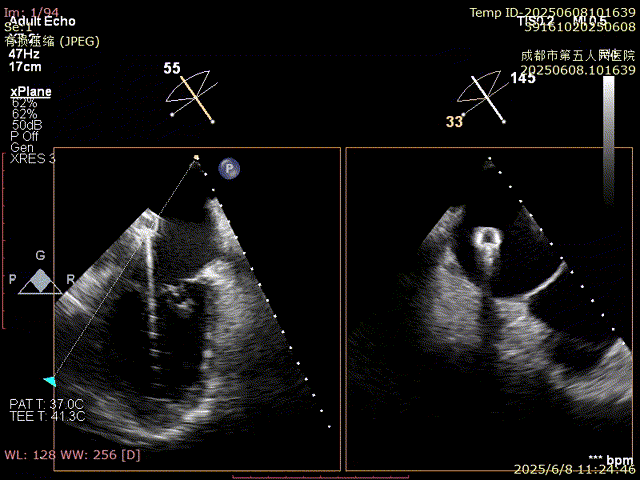

使用跨瓣器將16F鞘管送入心房

使用二尖瓣夾進行瓣葉捕獲,并進行夾合